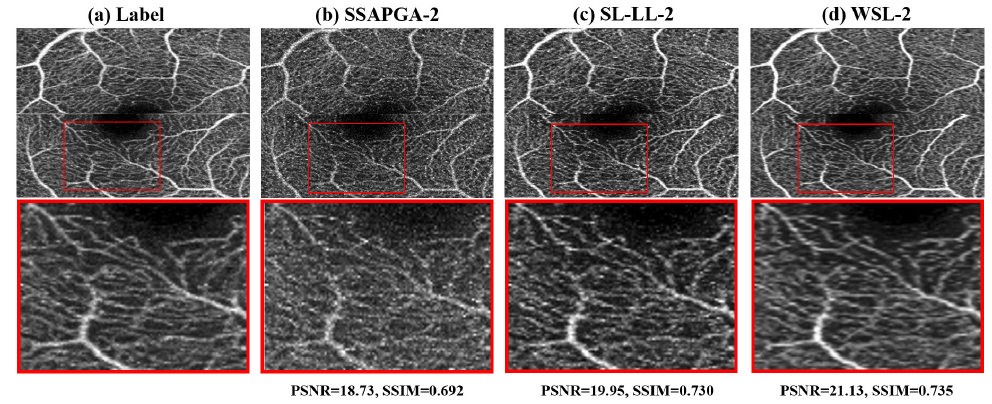

研究团队分别利用SD大鼠脑部血管造影数据和健康人眼数据对弱监督深度学习OCTA重建算法框架进行验证。提出的弱监督学习模型在SD大鼠数据集上展示了足以媲美基于高质量标签的监督学习算法的重建质量。不论是在噪声水平、对比度还是血管连续性上,均要明显好于目前最好的解析算法SSAPGA及基于低质量标签的监督学习算法,展现出良好的图像对比度和低散斑噪声水平。进一步,研究团队在人眼数据集上印证了在动物实验数据上得到的结论。这使得提出的弱监督学习算法具备了很好的临床应用前景。

图3. 弱监督深度学习OCTA重建算法及对照方法在人眼数据上的重建结果